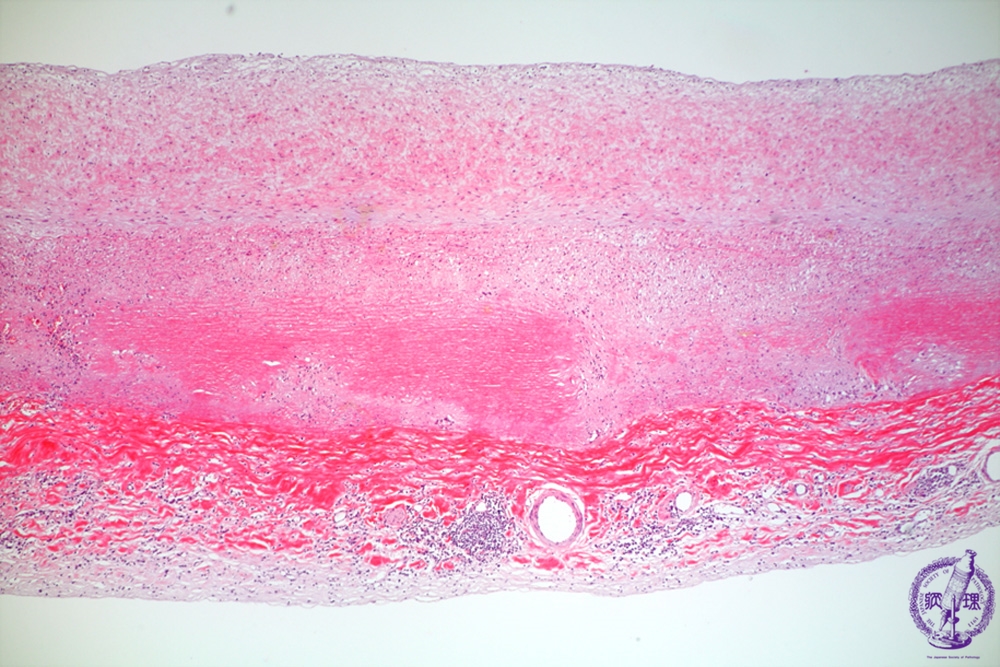

Microscopic image (HE, low power view): Prominent intimal and adventitial fibrous thickening and scarring.

Click the image to see the enlarged image.